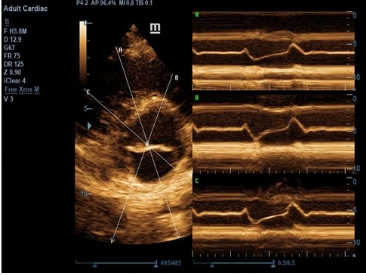

· 解剖M型Free Xros M

解剖M型能从任意角度进行扫描取样,对不同节段的心肌运动速度、

舒张-收缩时的心肌厚度变化进行细致的定量分析。